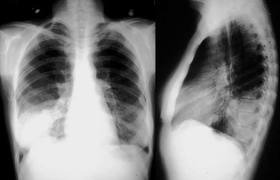

La evidencia disponible para la neumonía adquirida en la comunidad no internada en UTI y la exacerbación aguda de la EPOC respalda un tratamiento de corta duración de 5 días en pacientes que han mejorado clínicamente. Los esfuerzos de la comunidad científica deben dirigirse a implementar esta evidencia en la práctica diaria. Se necesitan ensayos de alta calidad para respaldar duraciones de tratamiento aún más cortas en estas y otras patologías respiratorias. The Lancet Infectious Diseases, 4 de septiembre de 2024.